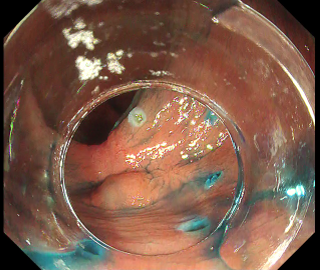

The importance of proper local injection is as described above, but proper “introduction into the submucosal layer”, i.e., entry of the scope tip beneath the mucosal flap, also leads to a favorable result, after which you simply proceed with dissection (Fig. 3). Merely incising the mucosa does not allow introduction into the submucosal layer, even if you try to insert the hood by force. Introduction into the submucosal layer may be possible after removing submucosal tissue a few times in the optimal manner, but this means that you must hold the proximal mucosa so that a large portion of the submucosal layer which you are going to cut is exposed, as shown in Fig. 4. In this figure, the mucosa is carefully held with the DualKnife J’s knob-shaped tip. A similar effect can be obtained by properly using the 6 o’clock position of the distal hood. Even so, it is still not easy to penetrate the layer with a single sweep.

Among the techniques that would facilitate introduction into the submucosal layer, one that can be used with DualKnife J is to “lift up with the tip”, as shown in Fig. 5. Lift the lesion flap with the sheath of DualKnife J and, after visually recognizing the submucosal layer you are going to cut, adjust the position as if aligning the knob-shaped tip with that line. The key here is to achieve maximum deaeration (introduction into the submucosal layer is impossible if the lumen is completely filled with insufflated air) and to gently lift the layer with the tip of the hood (Fig. 6).